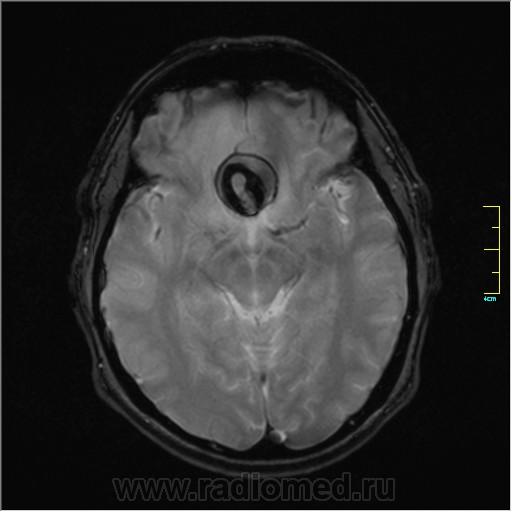

частично функционирующая аневризма

Иначе говоря, аневризма с хронической геморрагией, т.к. мы видим фракции крови различного возраста.

По-моему, аневризма с пристеночными тромбами.

Постепенное пристеночное образование тромбов приводит к появлению типичного для аневризмы феномена -слоистости МР сигнала в полости аневризмы. Данная картина демонстрирует слоистый характер тромботических масс в полости аневризмы .Функционрирующая часть имеет низкий сигнал во всех режимах сканирования. Дополнительно-перифокальный отек.

А может более корректно интерпретировать как частично тромбированная аневризма... Уж коь речь идет о фракциях, ну то есть о тромбе по сути.... Ну и плюс перфокальный отек головного мозга (вероятнее цитотоксический+вазогенный).